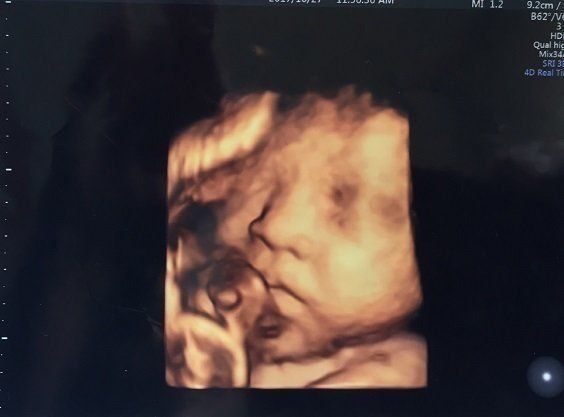

セイコさんの妊娠34週目のエコー写真 里帰り出産のため実家の産院へ移る

こちらの産院だと毎回4Dが撮ってもらえるので、楽しみです。かわいらしい手が結構はっきり写っています。手もほっぺもだいぶぷっくり?体重は2160g、頭の大きさは8.5㎝だそうです。

同じ日ですが、こちらはすごい顔で写っています。この週末は産院で行われた「パパママ育児クラス」に夫婦で参加しました。オムツの替え方、沐浴のさせ方、新生児に関するお話などを聞き、いよいよ本格的に出産の準備。パパたちが率先して挑戦していたのが、ほほえましかったです。